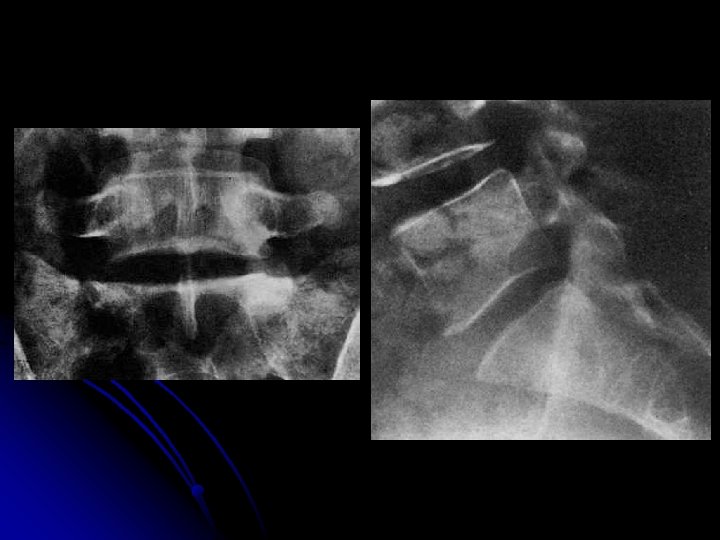

Rachis lombaire de face l Critères de réussite : l En haut : T 11 -T 12 l En bas: la symphyse pubienne et une partie des coxofémorales l Disques L 1 -L 2 à L 4 -L 5: enfilés.

l Statique rachidienne, l Morphologie: l des corps vertébraux, l des arcs postérieurs, et l’espace inter-arcual l Hauteur des espaces intervertébraux l Bords externes des psoas l Anomalie transitionnelle

Rachis lombaire de profil

l Statique rachidienne l Morphologie et structure des corps vertébraux, l Hauteur des espaces inter-vertébraux l Morphologie des arcs postérieurs